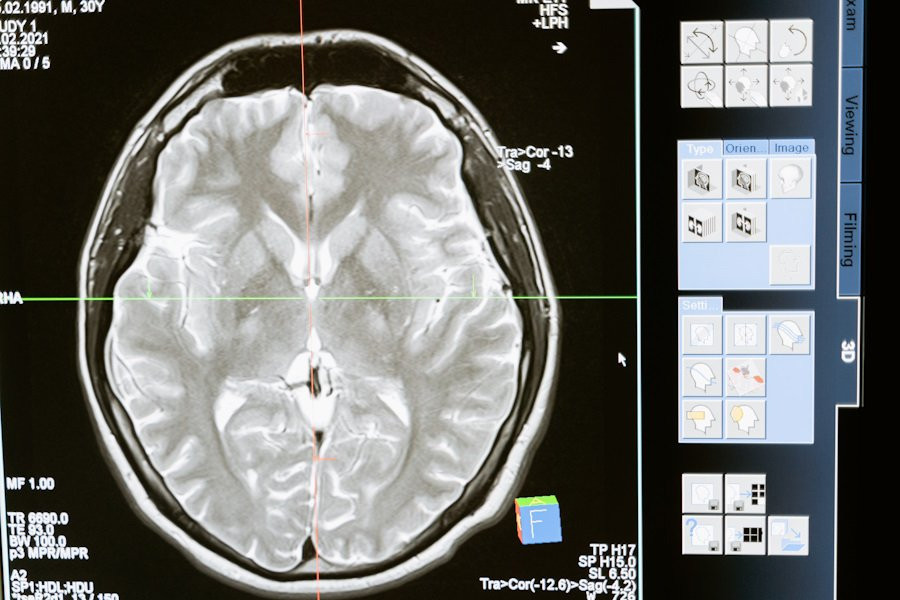

Учёные объединили методы нейровизуализации, включая функциональную магнитно-резонансную томографию (фМРТ), электроэнцефалографию (ЭЭГ) и функциональную спектроскопию в ближнем инфракрасном диапазоне (фНИРС), для оценки состояния пациентов в первые дни после травмы.